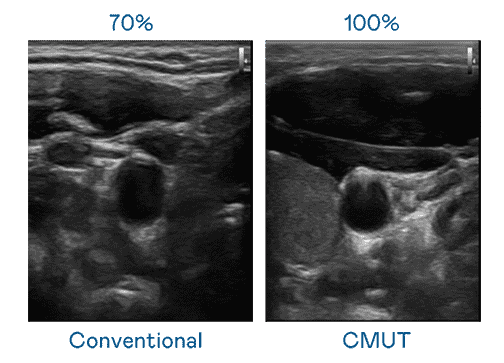

CMUT 技术是一种用电容式微机电元件来产生超音波讯号的技术。。。。与传统 PZT 压电式技术相比,,,CMUT 频宽增加 30%,,,,更宽频的超音波讯号让影像解析度大幅提升,,,是实现高影像品质医疗超音波扫描、、促进精准医疗发展的关键技术。。。。

大频宽带来超清晰影像

超音波影像的解析度高低,,首先取决于探头能发出的讯号频宽。。。。william威廉中文官网 CMUT 可提供高清晰的超音波讯号,,,提供高频宽、、、、高灵敏度、、、影像纹理细节更高的超音波影像,,,协助医护人员缩短影像判读时间及利用精准的医疗影像进行诊断。。。